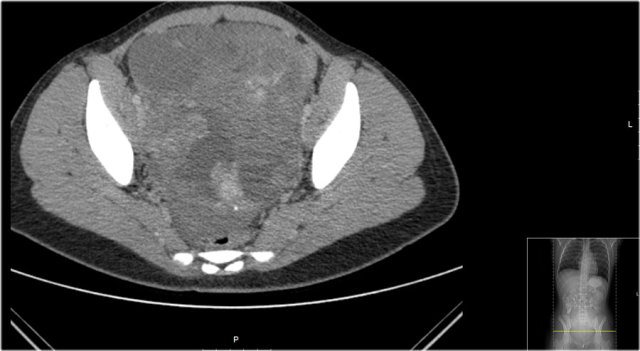

Here a CT-image of a 13-year-old girl presented with a lower abdominal mass.

It is a partly cystic, partly solid tumor with some calcifications.

The solid parts are inhomogeneous.

The tumor was resected and pathology showed a teratoma with malignant parts, with lymph node metastasis.